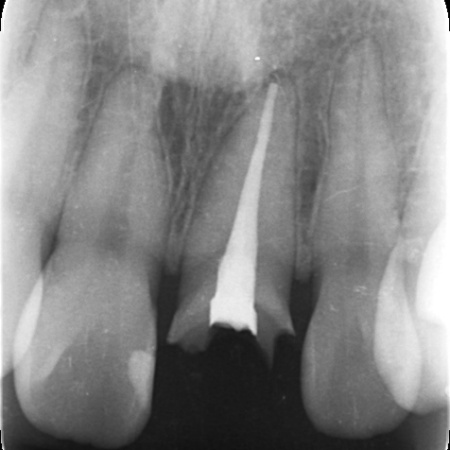

| カウンセリング | お口の中を拝見したところ、左上の前歯が大きく折れて被せ物を支える土台ごと外れていました。 レントゲン検査で確認した結果、歯の根自体には問題がなく炎症も見られなかったため、適切な治療を行えば歯を残せる状態であることが判明しました。 このまま放置した場合、残った歯根に細菌が入り込んで炎症を起こしたり、隣の歯に余計な負担がかかったりする可能性があります。 以上のことから、折れた歯を補う治療が必要と診断しました。 |

患者様は「できるだけ自分の歯のように自然な見た目にしてほしい」とご希望です。 そこで、白いグラスファイバーを用いた土台(ファイバーコア)に白い被せ物(ジルコニアセラミッククラウン)を装着する治療を提案し、同意いただきました。 ファイバーコアは光を通す素材のため自然な透明感があり、歯根への負担が少ないことが特徴です。 ジルコニアセラミッククラウンは、強度の高いジルコニアのフレームの上にセラミックを何層にも盛って焼き付けるレイヤリングを施した被せ物です。 治療初日は歯がないことで生じる不便さや見た目への影響に配慮し、その場で仮歯を作製して装着しました。 土台が完成したあとは歯科用顕微鏡のマイクロスコープで確認しながら、被せ物をスムーズに装着できるよう歯の形を丁寧に整えました。 その後、変形しにくいシリコン素材で精密な歯型を採取し、それをもとにジルコニアセラミッククラウンを作製しています。 |